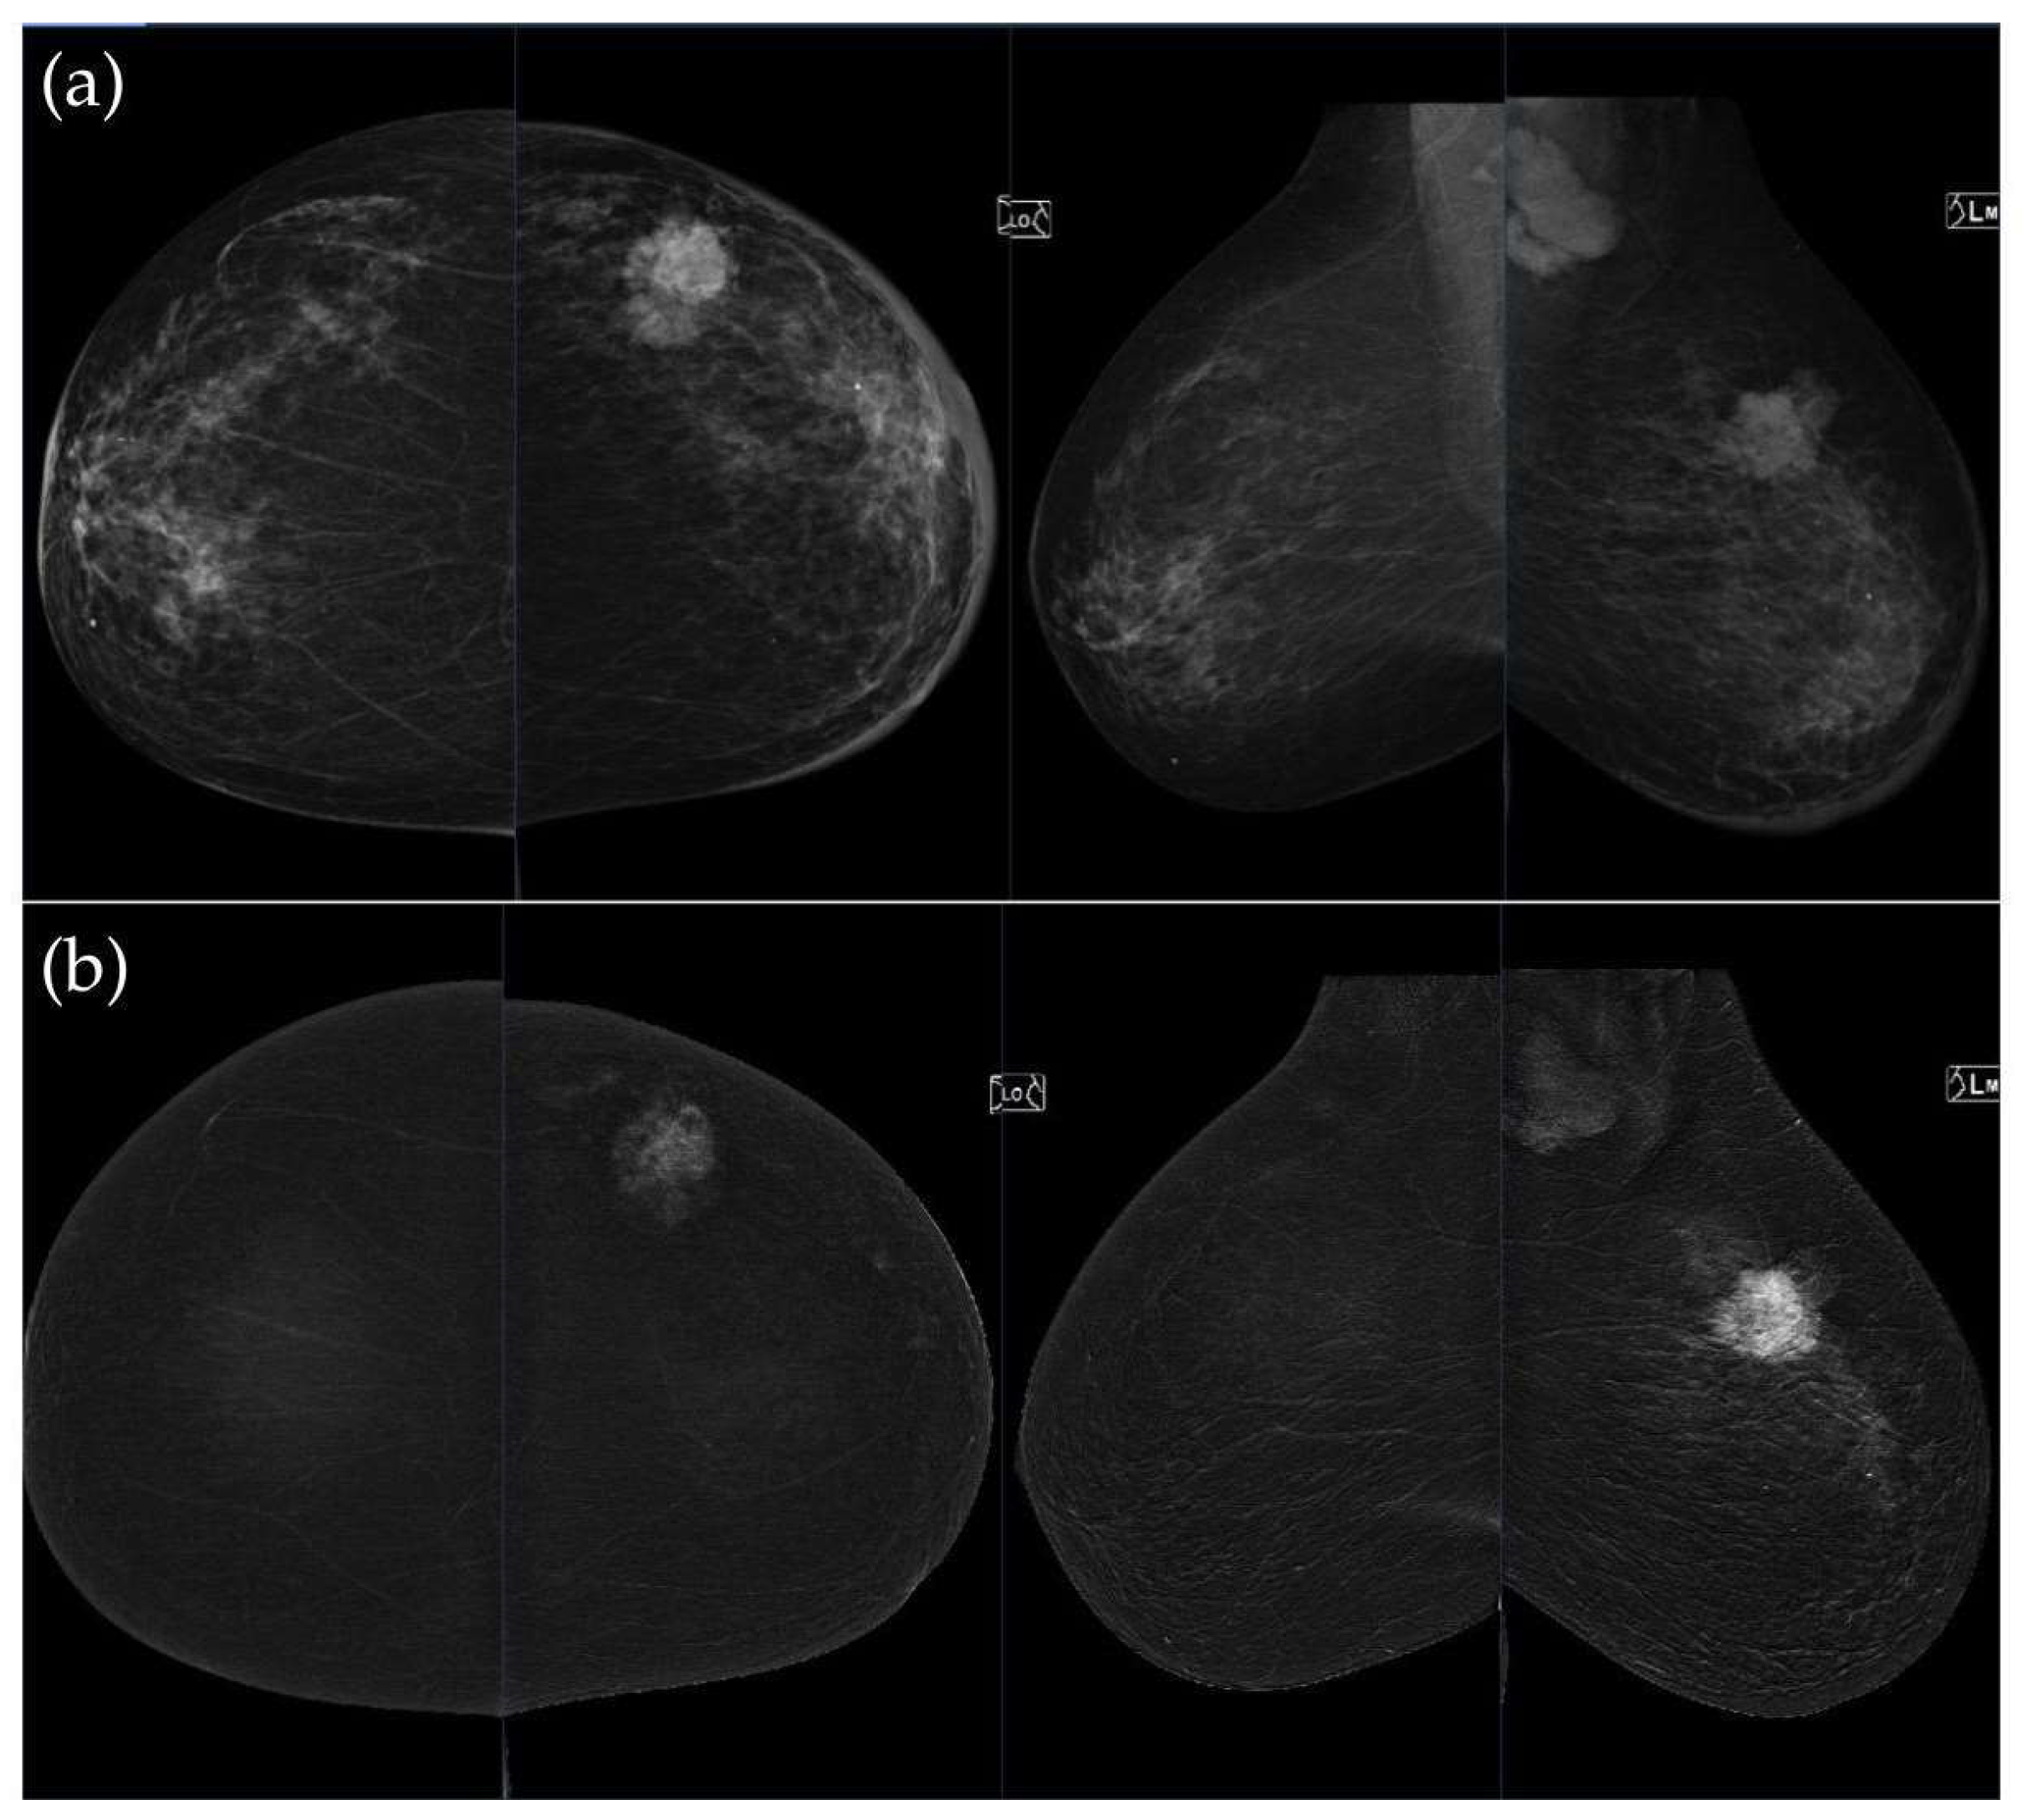

Figure 3, Figure 4, Figure 5 and Figure 6 present representative examples of CEM findings across molecular subtypes, with each case shown on both low-energy and recombined images.

To illustrate the behavior of the iCAD ProFound AI® system across different biological phenotypes, Figure 9 and Figure 10 present representative examples corresponding to Group 1 (luminal) and Group 2 (HER2-positive/triple-negative) tumors. In both cases, the algorithm correctly identified the lesion with high confidence and localized regions corresponding to malignant radiomic traits. These findings should be interpreted in the context of case-level AI assessment rather than lesion-specific prediction.

Figure 9. Example of iCAD ProFound AI® output for a luminal A carcinoma. The lesion detected on the low-energy image is automatically outlined by the AI system with an assigned malignancy probability. The outline shows the regions of highest AI attention, corresponding to irregular shape and spiculated margins, typical of luminal tumors.

Figure 10. Example of iCAD ProFound AI® output for a triple-negative breast carcinoma. The lesion detected on the low-energy image is automatically outlined by the AI system with an assigned malignancy probability. The outline shows the regions of highest AI attention, corresponding to oval shape and microlobulated, noncircumscribed margins.